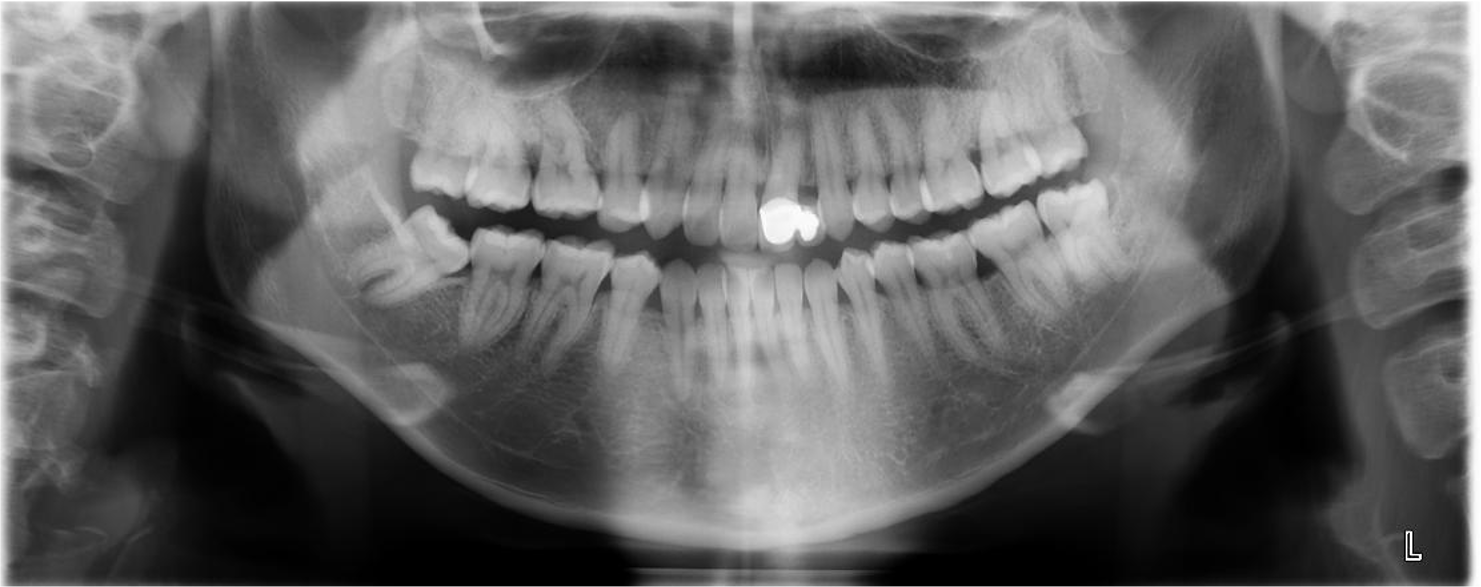

治療前,環口X光,深度蛀牙